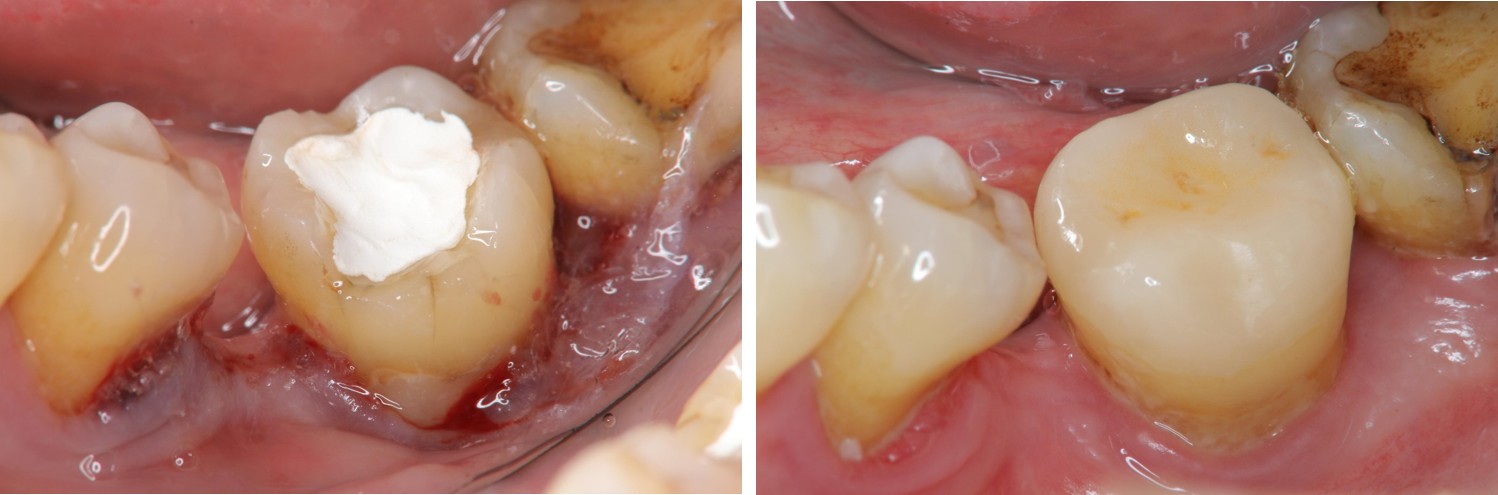

深度牙齦下蛀牙,可以使用雷射牙冠增長手術,將蛀牙的齒質移除,並進一步以複合樹脂填補。

水雷射牙冠增長手術及樹脂復形

治療後,功能與美觀恢復

術前、術後比較